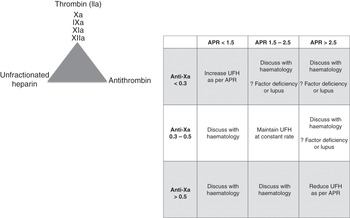

There is no universally agreed therapeutic range. It is a near-patient assay. Most hospitals have not validated their in-house ACT cartridges and do not know how this value correlates with their coagulation tests (which are highly variable from institution to institution). Each hospital should validate the ACT measurements to either their laboratory activated prothrombin time (aPTT) or anti-Xa measures to ensure that the adopted ACT range is at least comparable to the laboratory coagulation tests range. An example is shown in Figure 7.2. The ACT tests will vary in their sensitivity to heparin, and different systems should be used to monitor various clinical settings (e.g. an ACT system designed to be used during cardiac surgery will monitor much higher doses of heparin than systems used during ECMO).

Standard decision trees should be developed to support staff at the bedside. This should include when to call the haematology department (see example in Figure 7.3).

Figure 7.3 Example of a decision tree to support staff at the bedside. VA, veno-arterial; VV, veno-venous; PT, prothrombin time.